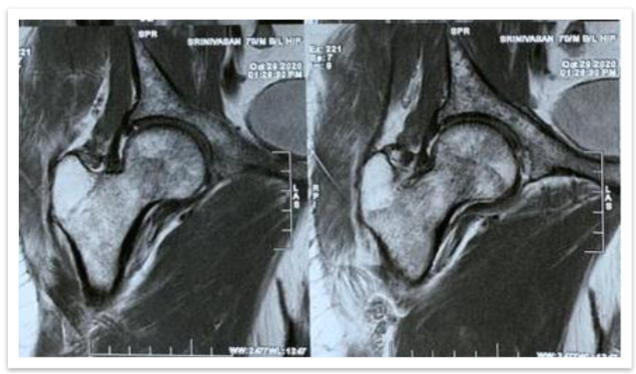

Serum protein electrophoresis was performed, and it was reported as normal (Figure 1). MRI was done to rule out any underlying pathology.

The MRI findings showed multiple focal altered signal intensity lesions (Figure 2). A bone biopsy was performed, and histopathological examination revealed the presence of plasma cells.